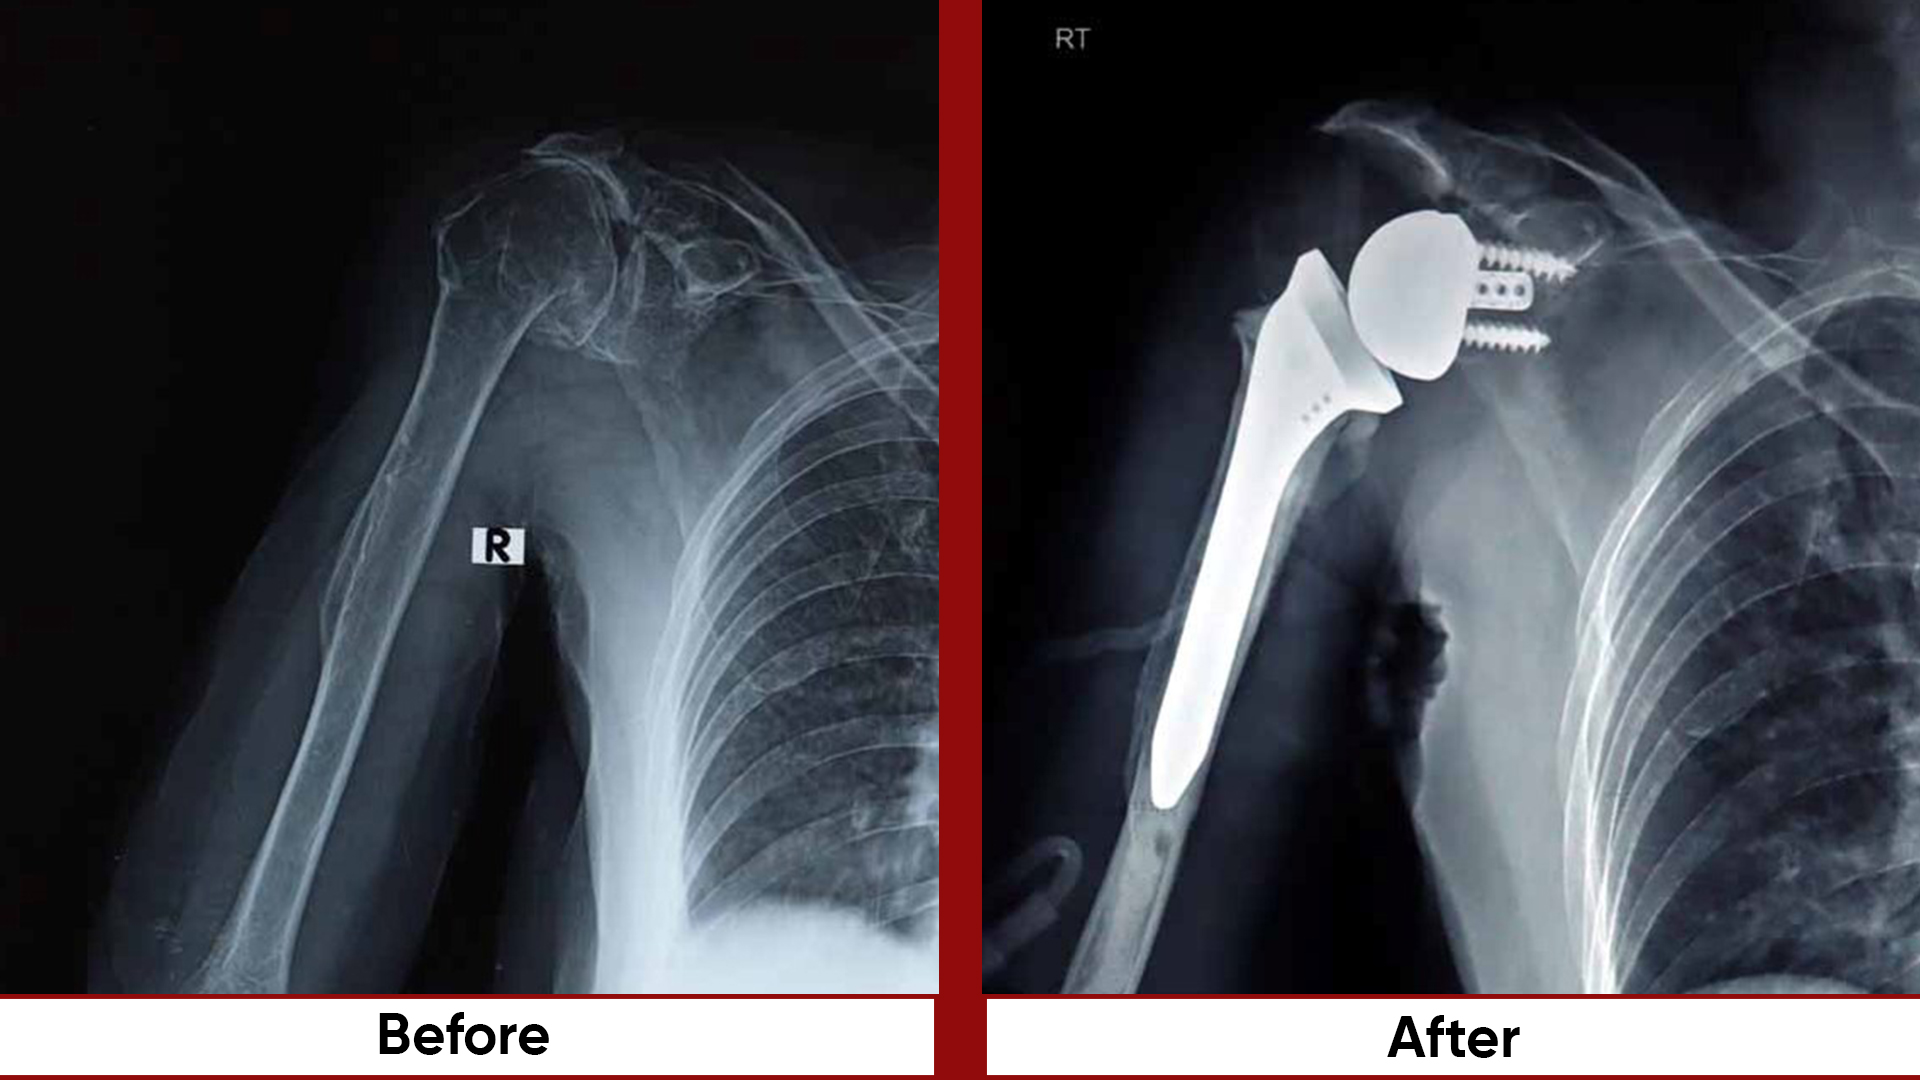

• Total Hip Replacement (THR)

• Arthroplasty